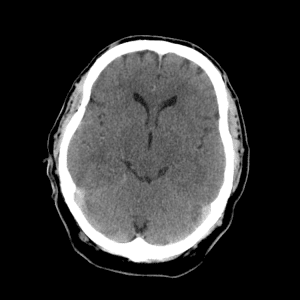

PICA infarct